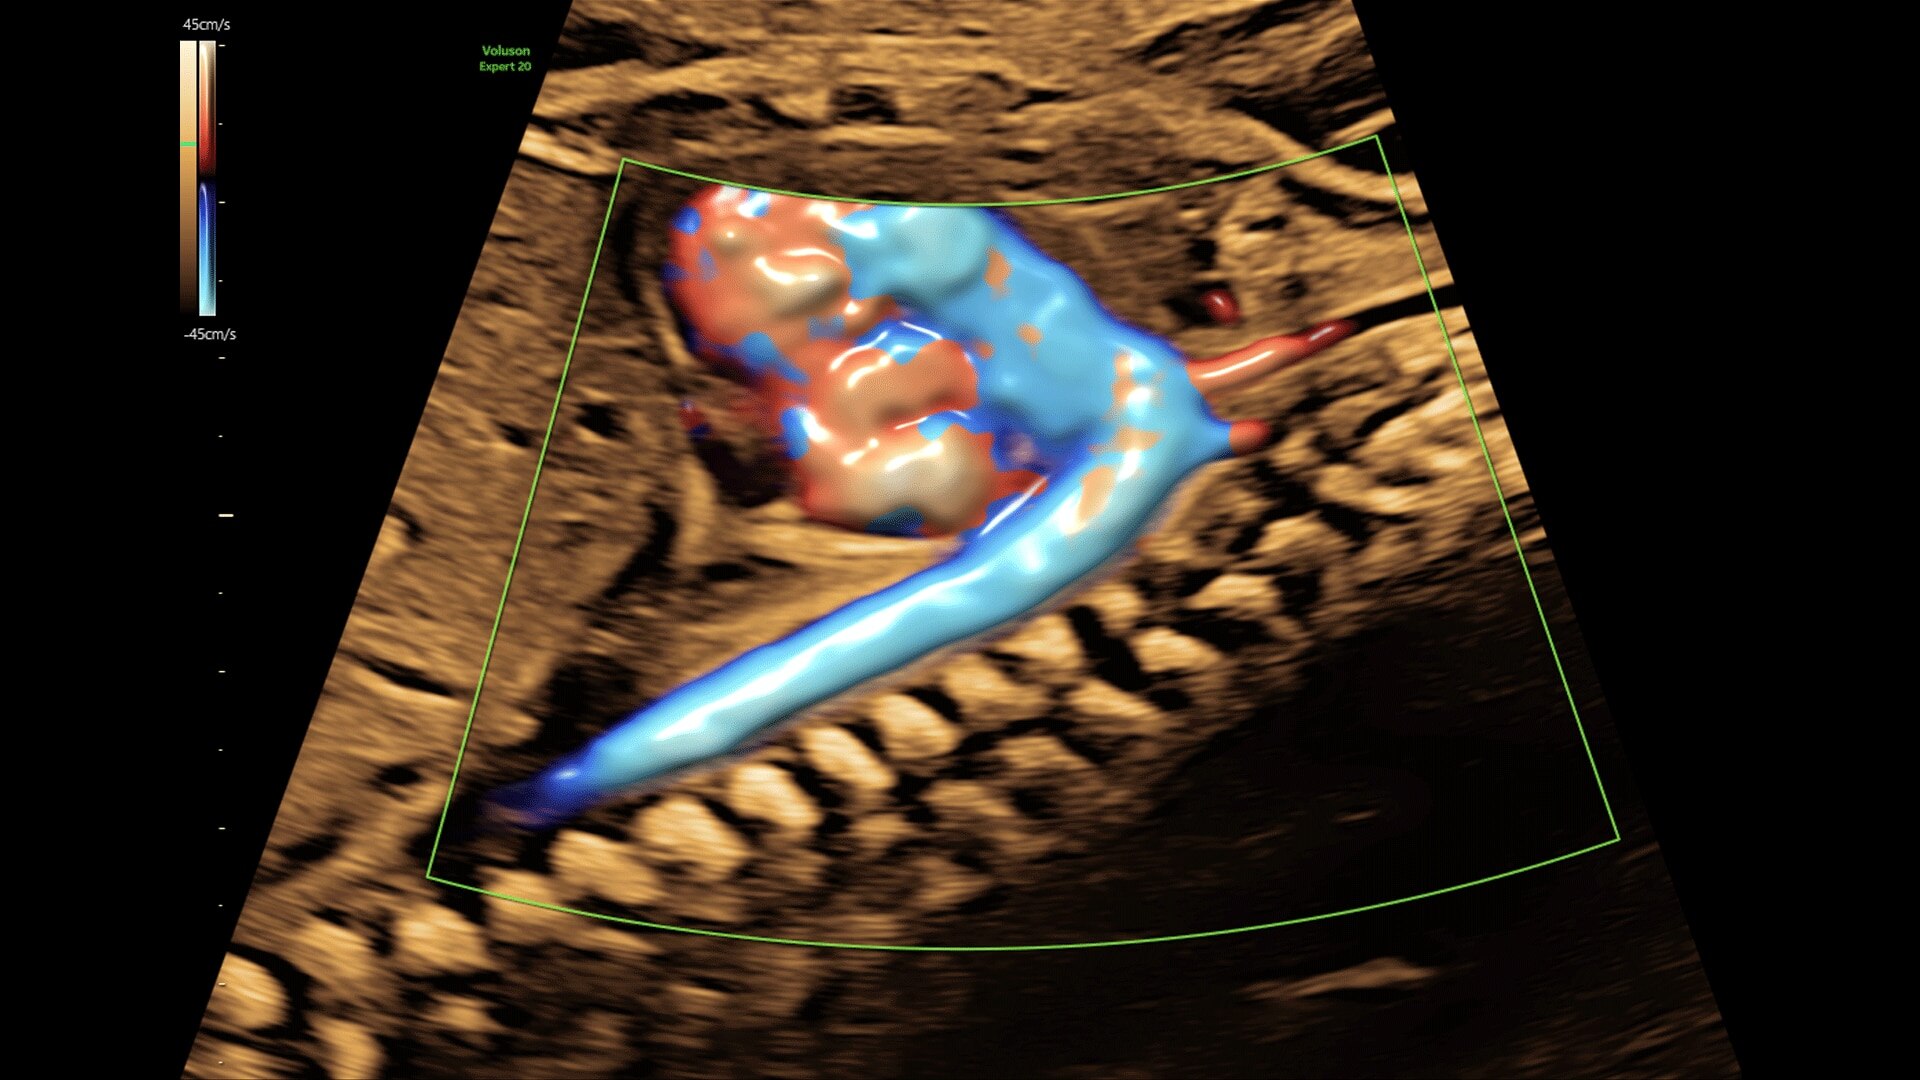

Generate spectacular 2D/3D and color Doppler images with increased penetration and stunning clarity, to help visualize critical details needed for diagnostic assurance. The Lyric Architecture unlocks new imaging and processing power to expand your imaging capabilities for years to come